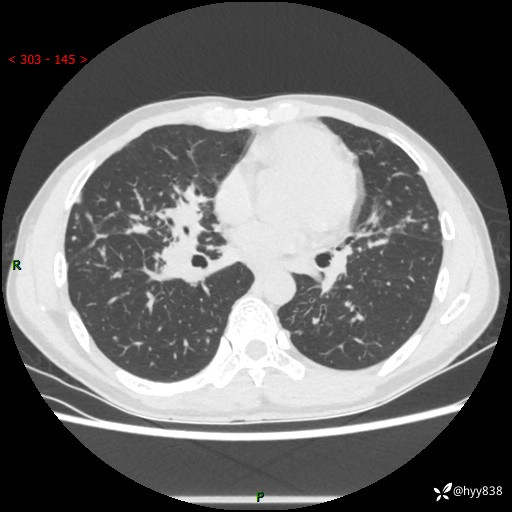

中年男性,咳嗽咳痰1月余。细看:肺、肺门、气管,貌似都有问题---(有结果)

现病史:患者于1个月前受凉后出现间断性咳嗽,伴白色泡沫样痰,无发热寒战、咯血、胸痛胸闷、恶心呕吐、呼吸困难等特殊不适,起初未予特殊处理,后患者就诊当地中医医院,查胸部CT提示支气管炎并双肺感染性病变,经抗感染(哌拉西林舒巴坦),止咳化痰(溴己新、三拗片)等治疗后,患者自诉咳嗽咳痰症状较前缓解,未诉发热等其他特殊不适,近期复查CT提示“肺部感染灶未见消退,双侧肺门增大,双肺散在小结节”,今为求进一步诊治,前来我院就诊,门诊以“肺部感染”收住入院。 患者自起病来精神、食欲、睡眠尚可,大小便正常,体力、体重无明显变化。

胸部CT平扫+增强(两期)